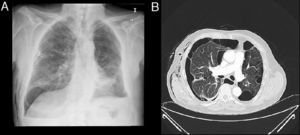

ProcedimientoLa colocación de las válvulas se realiza mediante broncoscopia flexible, bajo sedación consciente y anestesia local. La técnica de colocación de VEB parte de localizar el origen anatómico de la fuga. La fuga aérea se identifica previamente mediante la oclusión con balón durante una broncoscopia flexible (fig. 1A y B).

Localización de la fugaMediante un catéter con balón tipo Fogarty iremos ocluyendo los distintos segmentos o subsegmentos moviéndonos desde la parte proximal a la distal. Comenzamos ocluyendo el bronquio principal para demostrar que la fuga de aire desaparece. Si es así, se continúa taponando el bronquio lobar superior durante 1 a 3min mientras vamos observando el burbujeo en el sello de agua. Durante cada oclusión se recomienda esperar varios ciclos respiratorios (5 respiraciones) para determinar el efecto de la misma en la fuga aérea. Al ocluir el bronquio responsable de la fuga el burbujeo disminuirá o incluso desaparecerá10. Si no se aprecian cambios en el grado de la fuga aérea hay que ocluir el bronquio lobar inferior y, en el caso del pulmón derecho, el lobar medio al mismo tiempo. Una vez identificado el lóbulo diana, el paso siguiente es valorar cada segmento por separado. Este análisis sistemático del árbol bronquial nos permite localizar en la mayoría de las ocasiones la fuga, aunque esta sea debida a más de un segmento o más de un lóbulo11.